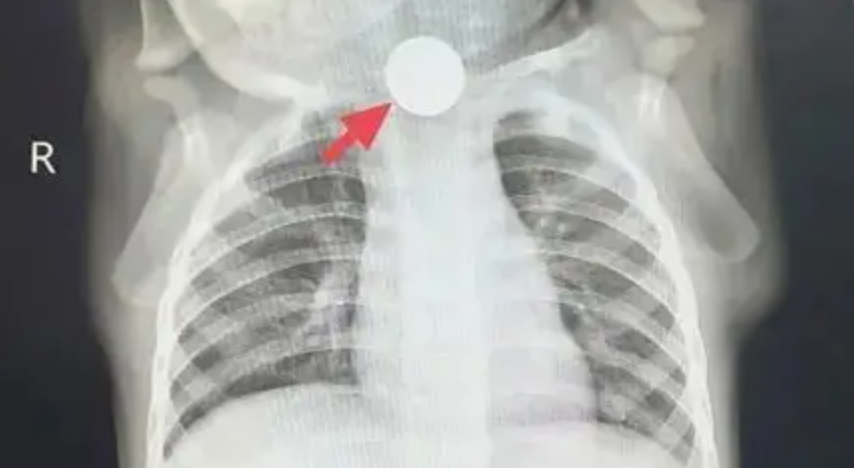

“Không thể chủ quan được, trước tiên cho bé chụp X-quang ngực để loại trừ vấn đề ở phổi!” - bác sĩ dặn gia đình. Thế nhưng, kết quả phim chụp mang lại không phải sự yên tâm, mà là một phát hiện khiến mọi người giật mình: ở đoạn trên thực quản của Đông Đông, có một đồng xu mắc kẹt!

Sự thật lập tức sáng tỏ: cái gọi là “chán ăn” thực chất là đồng xu mắc ở thực quản gây đau, khiến bé không thể ăn uống bình thường; chảy nước dãi là do dị vật chặn lại, nước bọt không nuốt xuống được; ho là phản xạ khi nước bọt tràn vào đường thở. Chẩn đoán trước đó là “chán ăn do ảnh hưởng tâm lý” hoàn toàn là nhận định sai lầm!

“Trẻ bị mắc một đồng xu trong thực quản đã gần một tuần, cần chuẩn bị nội soi lấy dị vật ngay!”. Sau khi nhận được thông báo khẩn, ê-kíp nội soi nhanh chóng vào vị trí, chuẩn bị kỹ lưỡng trước thủ thuật. Khi ống nội soi dạ dày được đưa vào, có thể thấy rõ đồng xu mắc ngang trong thực quản. Vùng niêm mạc xung quanh đã bị viêm đỏ, sưng phù, thậm chí xuất hiện ổ loét sâu, liên tục rỉ máu. Các bác sĩ thao tác hết sức cẩn trọng, chính xác gắp lấy đồng xu. Toàn bộ quá trình diễn ra trong không khí căng thẳng nhưng trật tự, cuối cùng đồng xu cũng được lấy ra thành công. Nhìn đồng xu vừa được gắp ra, bố mẹ Đông Đông vừa đau lòng vừa nhẹ nhõm, liên tục nắm tay bác sĩ cảm ơn.